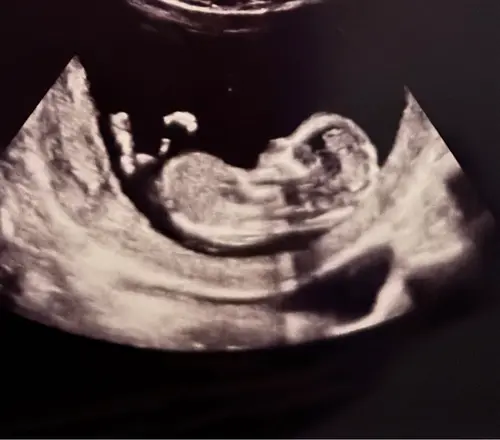

Ik had met de 13 weken echo hier een foto geplaatst waarop de Nub goed te zien was, bijna iedereen dacht dat het een meisje was waarvan een paar zelfs helemaal overtuigd. Twee personen zeiden een jongetje en wat bleek vandaag inderdaad een jongen 🤣😂😂.

Zo zie je maar de nub beoordelen zegt niet alles. We zijn hartstikke blij met een jongen overigens hoor! 😁😁